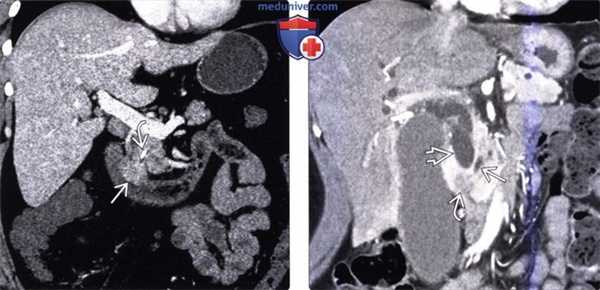

(Слева) На корональной КТ с контрастным усилением визуализируется полиповидное объемное образование (рак) в ампуле фатерова сосочка. Видна также часть билиарного стента ЕЕ. Изображения в корональной плоскости лучше всего позволяют визуализировать ампулу и оценить вероятное объемное образование.

(Справа) На корональной КТ с контрастным усилением визуализируется гиподенсное образование в ампуле, с нечеткими краями, вызывающие обструкцию общего желчного протока, при этом панкреатический проток расширен в незначительной степени. При оперативном вмешательстве был обнаружен рак ампулы фатерова сосочка.

(Слева) На корональной КТ с контрастным усилением (объемный рендеринг) определяется симптом «двойного протока» на фоне обструкции общего желчного и печеночного протоков, обусловленной полиповидным объемным образованием (рак) ампулы фатерова сосочка.

(Справа) На корональной КТ с контрастным усилением визуализируется дискретное объемное образование вокруг ампулы фатеровы сосочка, в которой находится билиарный стент. Рак ампулы сложно отличить от периампулярного рака двенадцатиперстной кишки методами визуализации, но, тем не менее, лечение в обоих случаях одинаково (операция Уиппла).